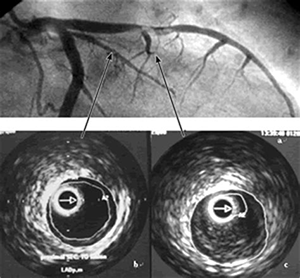

有研究显示,冠脉造影显示的轻度病变经IVUS检查证有部分实为严重病变,需要置人支架,证实了应用IVUS检查后显示冠脉造影低估病变的狭窄程度,且因造影不能区分病变的性质,而使不稳定斑块漏诊IVUS能够准确判断术前血管内病变的程度和范围,在支架置入前,为选择合适的支架提供准确的参考依据,使术者能够更好地选择支架的直径和长度,使支架和血管更好地匹配。在支架置入后,可对支架的大小、位置、形状、贴壁程度、对称性和展开满意度进行系统的评价,保证支架充分而不过度扩张。

冠脉造影只能根据对比剂在血管腔内的充填程度评价支架置入的效果,有时对比剂可渗透到支架外与血管壁的空隙中,常高估支架置入的效果。有研究证实,冠脉造影评价支架置入满意者,IVUS评价仍有88%的支架展开不完全,贴壁欠佳,需增加球囊直径或加大扩张压力。IVUS研究证实,冠脉造影在评价支架置入方面有一定的局限性,与支架为网孔样结构、支架与血管内膜之间残留间隙等造成造影效果满意的假象有关。同时IVUS可说明斑块的性质对支架置入效果的影响,软斑块比硬斑块有更大的扩张,硬斑块有更多的撕裂。